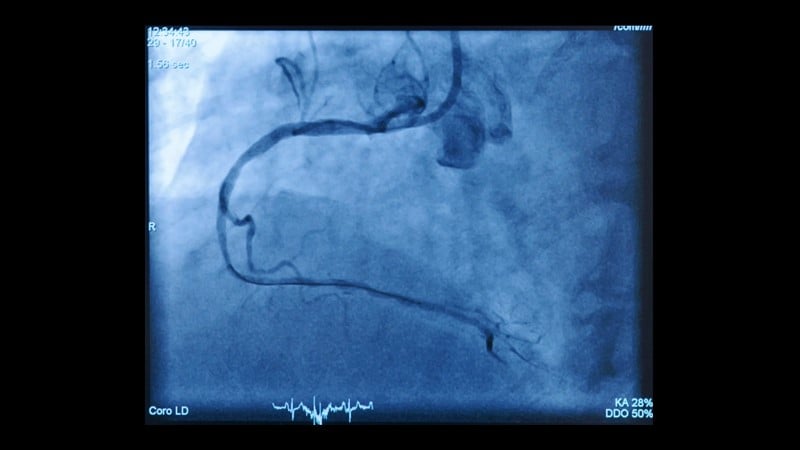

- To learn from a recorded case about robotic-assisted PCI procedural best practices and workflow